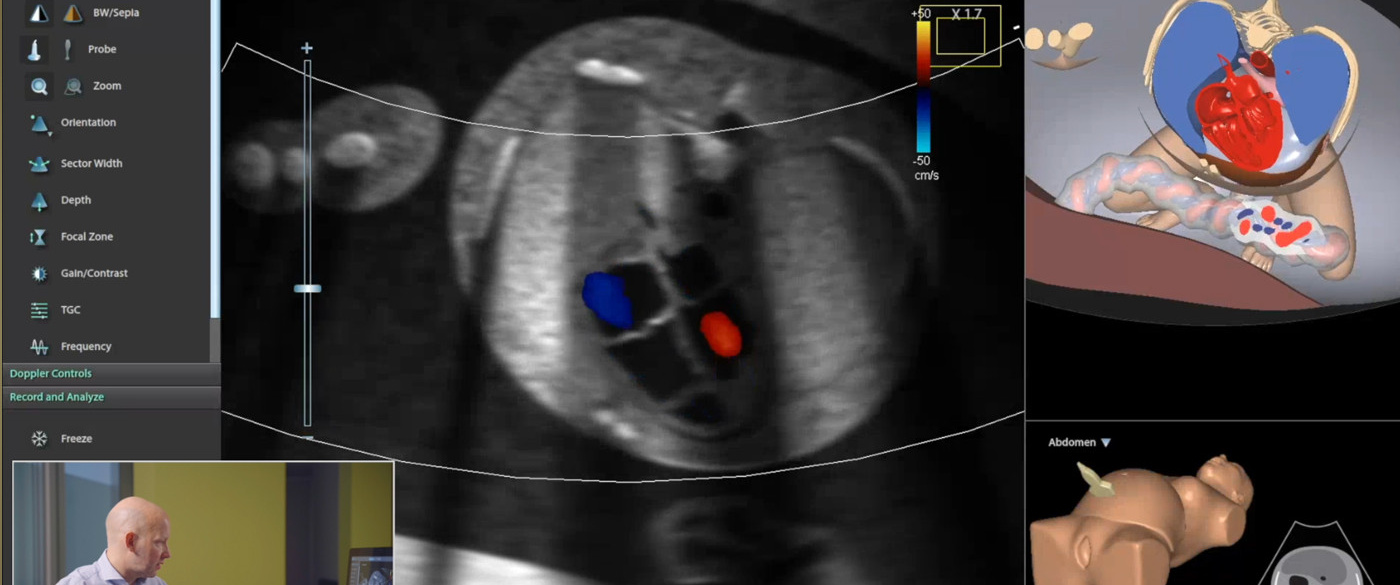

Mastering fetal echo training goes hand in hand with understanding the intricacies of imaging planes. Imaging planes are the key to visualizing the fetal heart from different angles, enabling practitioners to obtain comprehensive and accurate diagnostic information. Dr. Steinhard's presentation illustrated how various imaging planes are used to examine the fetal heart, providing a comprehensive view of its structure and function.

In the pursuit of excellence in fetal echo training, Dr. Steinhard's presentation introduced an existing approach used by multiple medical specialties, but with a potential to be more widely used within fetal echo training: simulator-based learning. The Ultrasound Mentor simulator by Surgical Science was highlighted as a powerful tool for training medical professionals in mastering fetal echo techniques.